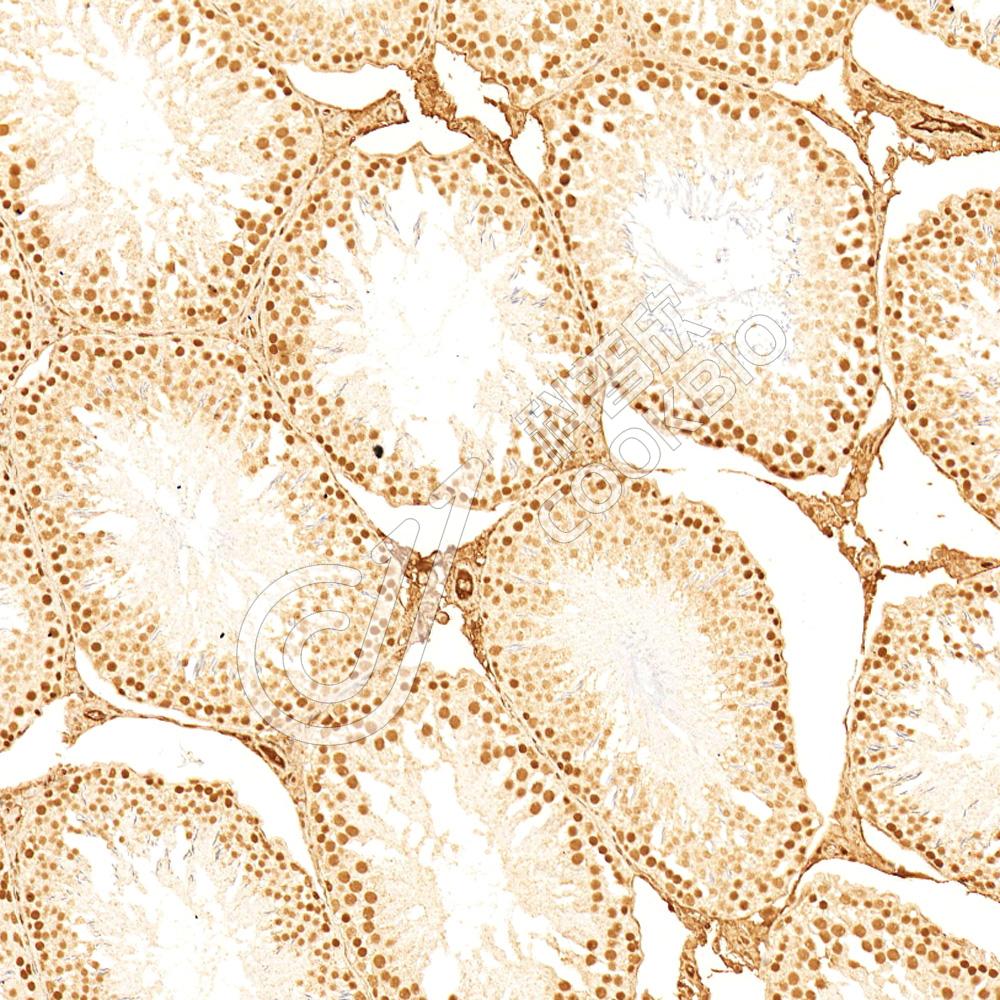

IHC检测METTL3蛋白(货号 K2374064).

样品: 大鼠卵巢, 4%多聚甲醛 (货号KSG1101) 固定12-24小时.

抗原修复: 柠檬酸抗原修复液(干粉, pH 6.0) (KSG1201), 高压锅均匀喷气计时2分钟.

—抗: 1: 800稀释, 4℃ 孵育过夜.

二抗: S-vision免疫组化多聚二抗(山羊抗小鼠), 即用型(货号KB3903), 室温孵育20分钟.